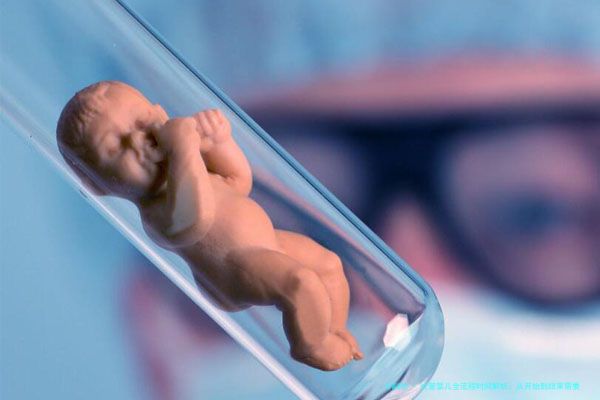

试管婴儿,作为现代辅助生殖技术的代表,已经帮助无数家庭圆了生育梦想。但很多人在考虑这条路时,心里都会打鼓:整个过程到底要花多长时间?会不会拖上好几个月甚至更久?今天,咱们就来详细聊聊试管婴儿的全流程,从第一步到最后一步,看看时间都去哪儿了。说实话,这就像一场精心策划的旅程,每个环节都环环相扣,但具体时长还得看个人情况和诊所安排。一般来说,从启动到知道结果,整个过程可能需要2到4个月左右,但别急,我会分步骤帮你捋清楚。

试管婴儿可不是说做就能做的,首先得做好充分的准备工作。这个阶段就像盖房子前的地基勘察,至关重要。通常,夫妻双方需要去医院进行全面的身体检查,包括激素水平、输卵管状况、精子质量等,以确保适合进行试管婴儿。医生还会安排心理咨询,帮助缓解焦虑情绪。根据我的经验,这个过程可能需要1到2周,因为有些检查结果需要时间才能出来,比如染色体分析。有时候,如果发现潜在问题,比如子宫内膜异位或卵巢功能下降,医生可能建议先治疗,这样时间就会延长。举个例子,我的朋友李姐,她在备孕时发现输卵管堵塞,花了额外一个月调理身体,才进入下一阶段。所以,前期准备是弹性最大的部分,但别担心,这是为了后续流程更顺利。

一旦评估通过,就会进入促排卵阶段。这是试管婴儿的核心步骤之一,目的是通过药物刺激卵巢,让多个卵泡同时发育。这个过程通常需要10到14天,但具体时间因人而异。医生会根据你的身体反应,调整药物剂量,并通过B超和血液检查密切监测卵泡生长。我记得有个案例,王女士因为卵巢反应较慢,促排卵用了近3周,但最终还是成功取卵。这个阶段需要频繁去医院,但为了收获更多优质卵子,这些时间投入是值得的。另外,医生可能会建议使用辅助药物来优化卵子质量,这也会稍微影响时间线。总的来说,促排卵阶段就像一场“时间赛跑”,但好的诊所会精准把控,确保效率。

当卵泡成熟后,就会安排取卵手术,这通常是一个简短的门诊手术,只需一天就能完成。取卵的同时,男方也会提供精子样本。接下来,实验室里的“魔法”就开始了:卵子和精子在体外结合,形成胚胎。胚胎培养阶段大约需要3到5天,医生会观察胚胎发育情况,并可能进行基因筛查(PGT),这能提高成功率,但也会增加1到2周的时间。我个人的观点是,这个阶段虽然时间不长,但却是决定成败的关键,所以选择技术先进的实验室很重要。比如,有些诊所采用先进的培养技术,能更快筛选出健康胚胎,节省整体时间。胚胎培养后,如果有合适的胚胎,就可以进入移植环节。

胚胎移植是另一个关键步骤,通常也是一个快速的手术,只需几分钟就能完成。移植后,你需要等待大约10到14天进行妊娠测试,看看是否成功着床。这个等待期可能感觉特别漫长,但保持放松心态很重要。如果测试成功,恭喜你!接下来就是常规的产检流程;如果不成功,可能需要重新开始或调整方案,这自然会延长整体时间。根据统计,一次试管婴儿周期从开始到妊娠测试结果出来,平均耗时2到3个月。但请记住,这只是一个平均值,实际时间可能因个人健康状况、诊所排队情况等因素而异。比如,在繁忙的生殖中心,预约移植可能要多等几周,所以建议提前规划。

综合来看,试管婴儿的全流程从前期准备到妊娠测试,通常需要2到4个月左右。但这个时间不是固定的,它像一条有弹性的绳子,会随着各种因素拉伸或缩短。影响时间的因素包括:年龄(年轻女性往往恢复更快)、身体状况(如卵巢反应、子宫环境)、诊所效率(如预约等待时间),以及是否需要进行额外步骤,如冷冻胚胎移植。我个人认为,心态调整也很关键——别把时间当成压力,而是看作一个精心准备的过程。有些夫妇可能一次就成功,全程只花2个多月;而另一些人可能需要多个周期,时间就会拉长到半年或更久。所以,提前咨询医生,制定个性化计划,能帮助你更好地管理时间预期。